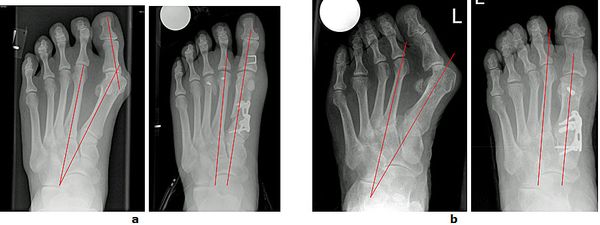

Abb.4: Klinische Dokumentation einer mittelschweren Hallux valgus Fehlstellung.

a Vor der Operation

b Rechter Fuß 7 Wochen postoperativ und linker Fuß 6 Monate postoperativ